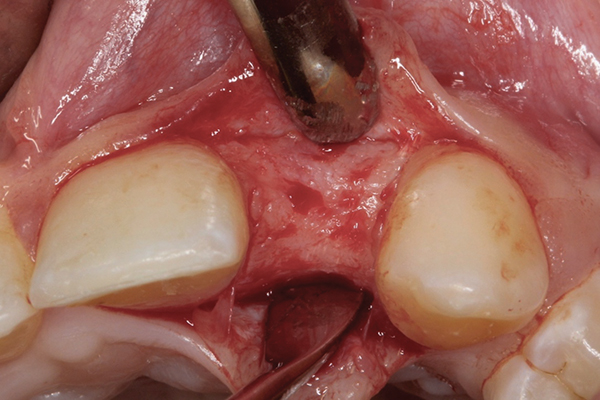

When the patient was age 17 years and 5 months, a cone-beam computed tomography (CBCT) scan30 was taken that revealed she had only 4.5-mm thickness of buccal/palatal alveolar ridge. The periodontist recommended lateral ridge augmentation to provide an additional 3 mm to 4 mm to achieve a stable long-term result.22,31 A root concavity on fused teeth Nos. 7 and 8 was also detected, which was thought to pose a complication for achievement of optimal gingival health.11 Alveolar bone augmentation of the buccal ridge at site No. 10 was performed. Following 6 months of healing, the second lateral cephalometric radiograph was taken by the orthodontist to verify cessation of somatic growth.29,31-33 Alginate impressions were taken by the prosthodontist to construct a surgical stent,34 and the final treatment plan was confirmed. As a result of the esthetic success achieved by the interim composite restoration, a lithium disilicate veneer35 using gingival porcelain to restore the missing interproximal papilla was proposed for fused teeth Nos. 7 and 8. The patient also requested a veneer for the adjacent central incisor, tooth No. 9. A ceramic implant crown and custom abutment were planned for site No. 10.

Following soft-tissue maturation, the desired shades with characterization were selected including the gingival shade for the pink porcelain, and fused teeth Nos. 7 to 8 and tooth No. 9 were prepared for veneers (Figure 11). Care was taken to dip into the preparation facially at the interface between the proposed central-lateral teeth, and shorten the distal-incisal to provide room for the laboratory to create the appearance of two separate teeth with a shorter lateral incisor. Retraction cord was placed for gingival displacement, the zirconia coping was inserted on the implant abutment, and an impression of the fused teeth Nos. 7 and 8 and tooth No. 9 was made, picking up the zirconia coping (Figure 12).

Fig 11. Fused teeth Nos. 7 and 8 and tooth

No. 9 were prepared for veneers.

Fig 12. Impression of the fused teeth Nos. 7 and 8 and tooth No. 9.